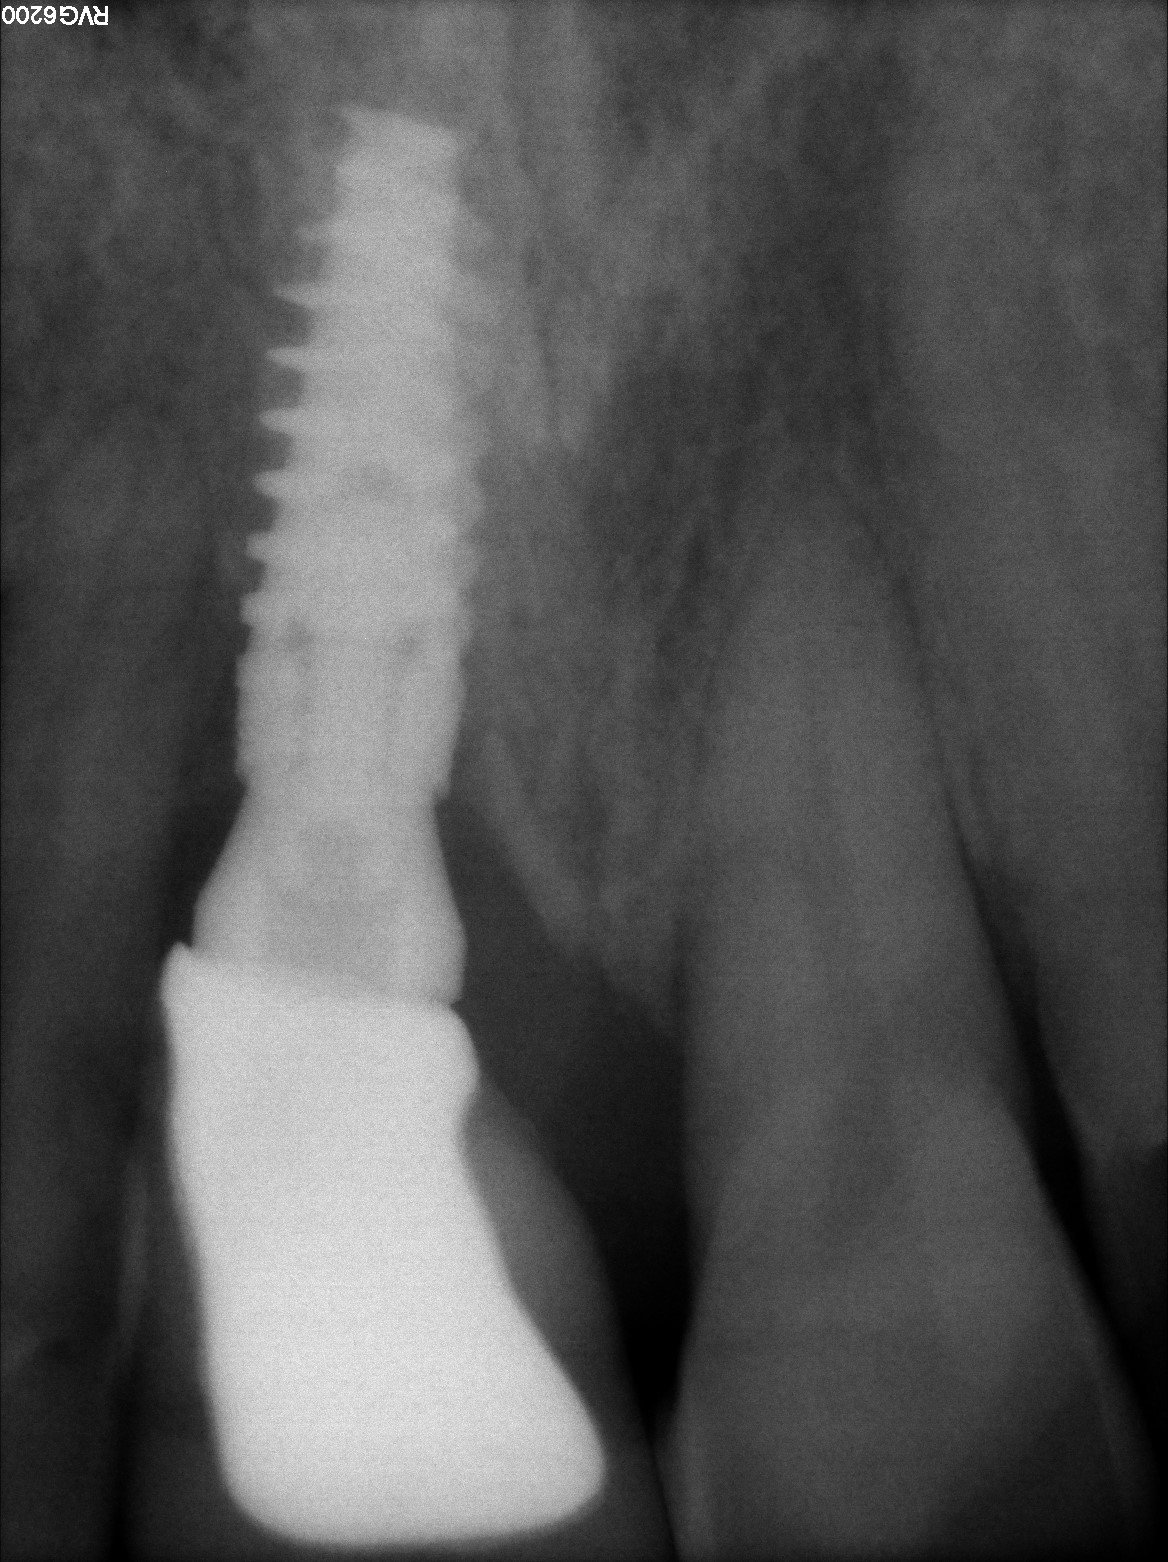

Implante 47

Buenos días, nos ha llegado este caso en el que tenemos que cambiar la corona del 47, ¿sabríais decirme de qué implante se trata?, ¿sabéis si hay aditamentos para escanear [...]